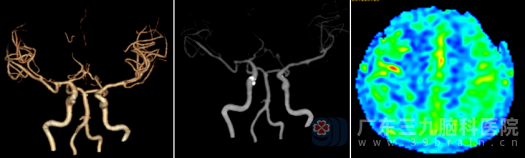

为求进一步诊治,陈女士及家人慕名来到广东三九脑科医院神经外十科。入院后,术前CTA检查提示:右侧大脑中动脉及双侧大脑前动脉起始部重度狭窄-基本闭塞,周围侧枝循环增多(造影片上看上去像烟雾)。ASL脑灌注检查更是显示:双侧额顶叶存在明显的缺血或灌注延长,右侧尤为严重。